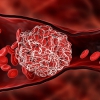

![]() Thiếu máu não là tình trạng máu lưu thông lên não kém dẫn đến không cung cấp đủ dinh dưỡng và oxy cần thiết cho các hoạt động của não

Thiếu máu não là tình trạng máu lưu thông lên não kém dẫn đến không cung cấp đủ dinh dưỡng và oxy cần thiết cho các hoạt động của não